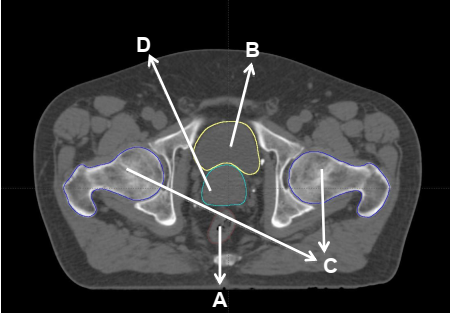

Em planejamento de radioterapia conformacional são utilizadas imagens tomográficas para delimitar os órgãos sadios (órgãos de risco), em que a dose deve ser minimizada para diminuir os efeitos colaterais do tratamento, e a região de tratamento (volume alvo), em que a dose de tratamento é prescrita. Analise a figura a seguir, utilizada em planejamento de um tumor de próstata inicial.

Sobre as estruturas marcadas na figura e considerando o disposto anteriormente, assinale a afirmativa correta.